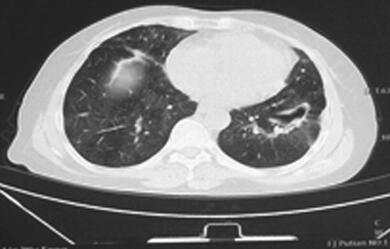

入院后检查:生命体征尚平稳,急性病容,呼吸急促,有发热,体温38.6℃,双肺散在湿性啰音。心律齐,心率快,114次/分,各瓣膜听诊区未闻及杂音,腹部无明显阳性体征,双下肢无水肿。脑膜刺激征阴性,病理征未引出。血常规:WBC 18.3×109/L,N% 94.1%,HGB 108g/L,PLT 130×109/L。红细胞沉降率:96mm/h。PCT 18.7ng/ml,BNP 15 200pg/ml,肝肾功能未见明显异常。低钠血症,低钾血症,结核菌素试验(+)。3次痰抗酸染色未见抗酸杆菌。3次痰培养未发现致病菌。血气分析(吸氧2L/M)提示:pH 7.492,PaO2 59.3mmHg,PaCO2 16.3mmHg。抗核抗体(ANA)、ANA谱、dsDNA抗体及抗中性粒细胞抗体均正常。钩端螺旋体抗体、恙虫病抗体、流行性出血热抗体均阴性。真菌D-葡聚糖+曲霉菌半乳甘露聚糖抗原:均正常。HAV+HIV+HCV+TPPA抗体:均正常。呼吸道感染病原体IgM抗体:呼吸道合胞病毒-IgM抗体阳性(+),余均阴性。(2014年6月29日)肺部CT平扫(图1):):①双肺弥漫性病变伴空洞形成,肺炎并脓肿?肉芽肿性病变?②左下肺脓肿形成。

图1 2014年6月29日胸部HRCT

双肺弥漫性病变伴空洞形成,左下肺脓肿形成